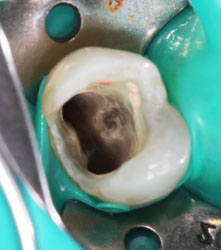

Ко мне обратилась пациентка с просьбой попробовать «спасти» нижний 6-ой зуб от удаления. Вот так он выглядел в полости рта.

Что мы здесь видим? Ну, во-первых, напрочь отсутствующую анатомию зуба. Огромная полость заштукатурена (другого слова и не подберешь) без малейшей попытки создать на зубе необходимый для жевания рельеф поверхности с бугорками и бороздками между ними. Через материал просвечивает анкерный штифт, который призван удерживать эту «нашлепку» внутри зуба. Во-вторых, по краям пломбы заметно прокрашивание границы, т.е. пломба уже давно негерметична, а, значит, внутрь просачивается микрофлора полости рта, вызывая рецедив кариеса и воспалительный процесс в костной ткани вокруг корня. В-третьих, мы можем видеть только 2 сохранившихся стенки собственного зуба, которые к тому же изрядно истончены. Учитывая, что зуб давно мертвый, методика реставрации явно выбрана неудачная. Да и исполнена при этом весьма скверно. Дело в том, что наши жевательные зубы испытывают достаточно серьезные нагрузки при жевании (по разным данным около 100 кг на см2), и оставшиеся тонике стеночки в любой момент могут треснуть. Нередко трещина уходит глубоко под десну и в итоге зуб приходится удалять. Поэтому если зуб депульпирован и имеет значительные разрушения (как в нашем случае), то его нужно обязательно восстанавливать коронкой. Только в этом случае Вы будете застрахованы от любых неприятных сюрпризов. Но для данного зуба это только полбеды. Не меньшая проблема содержалась и внутри.